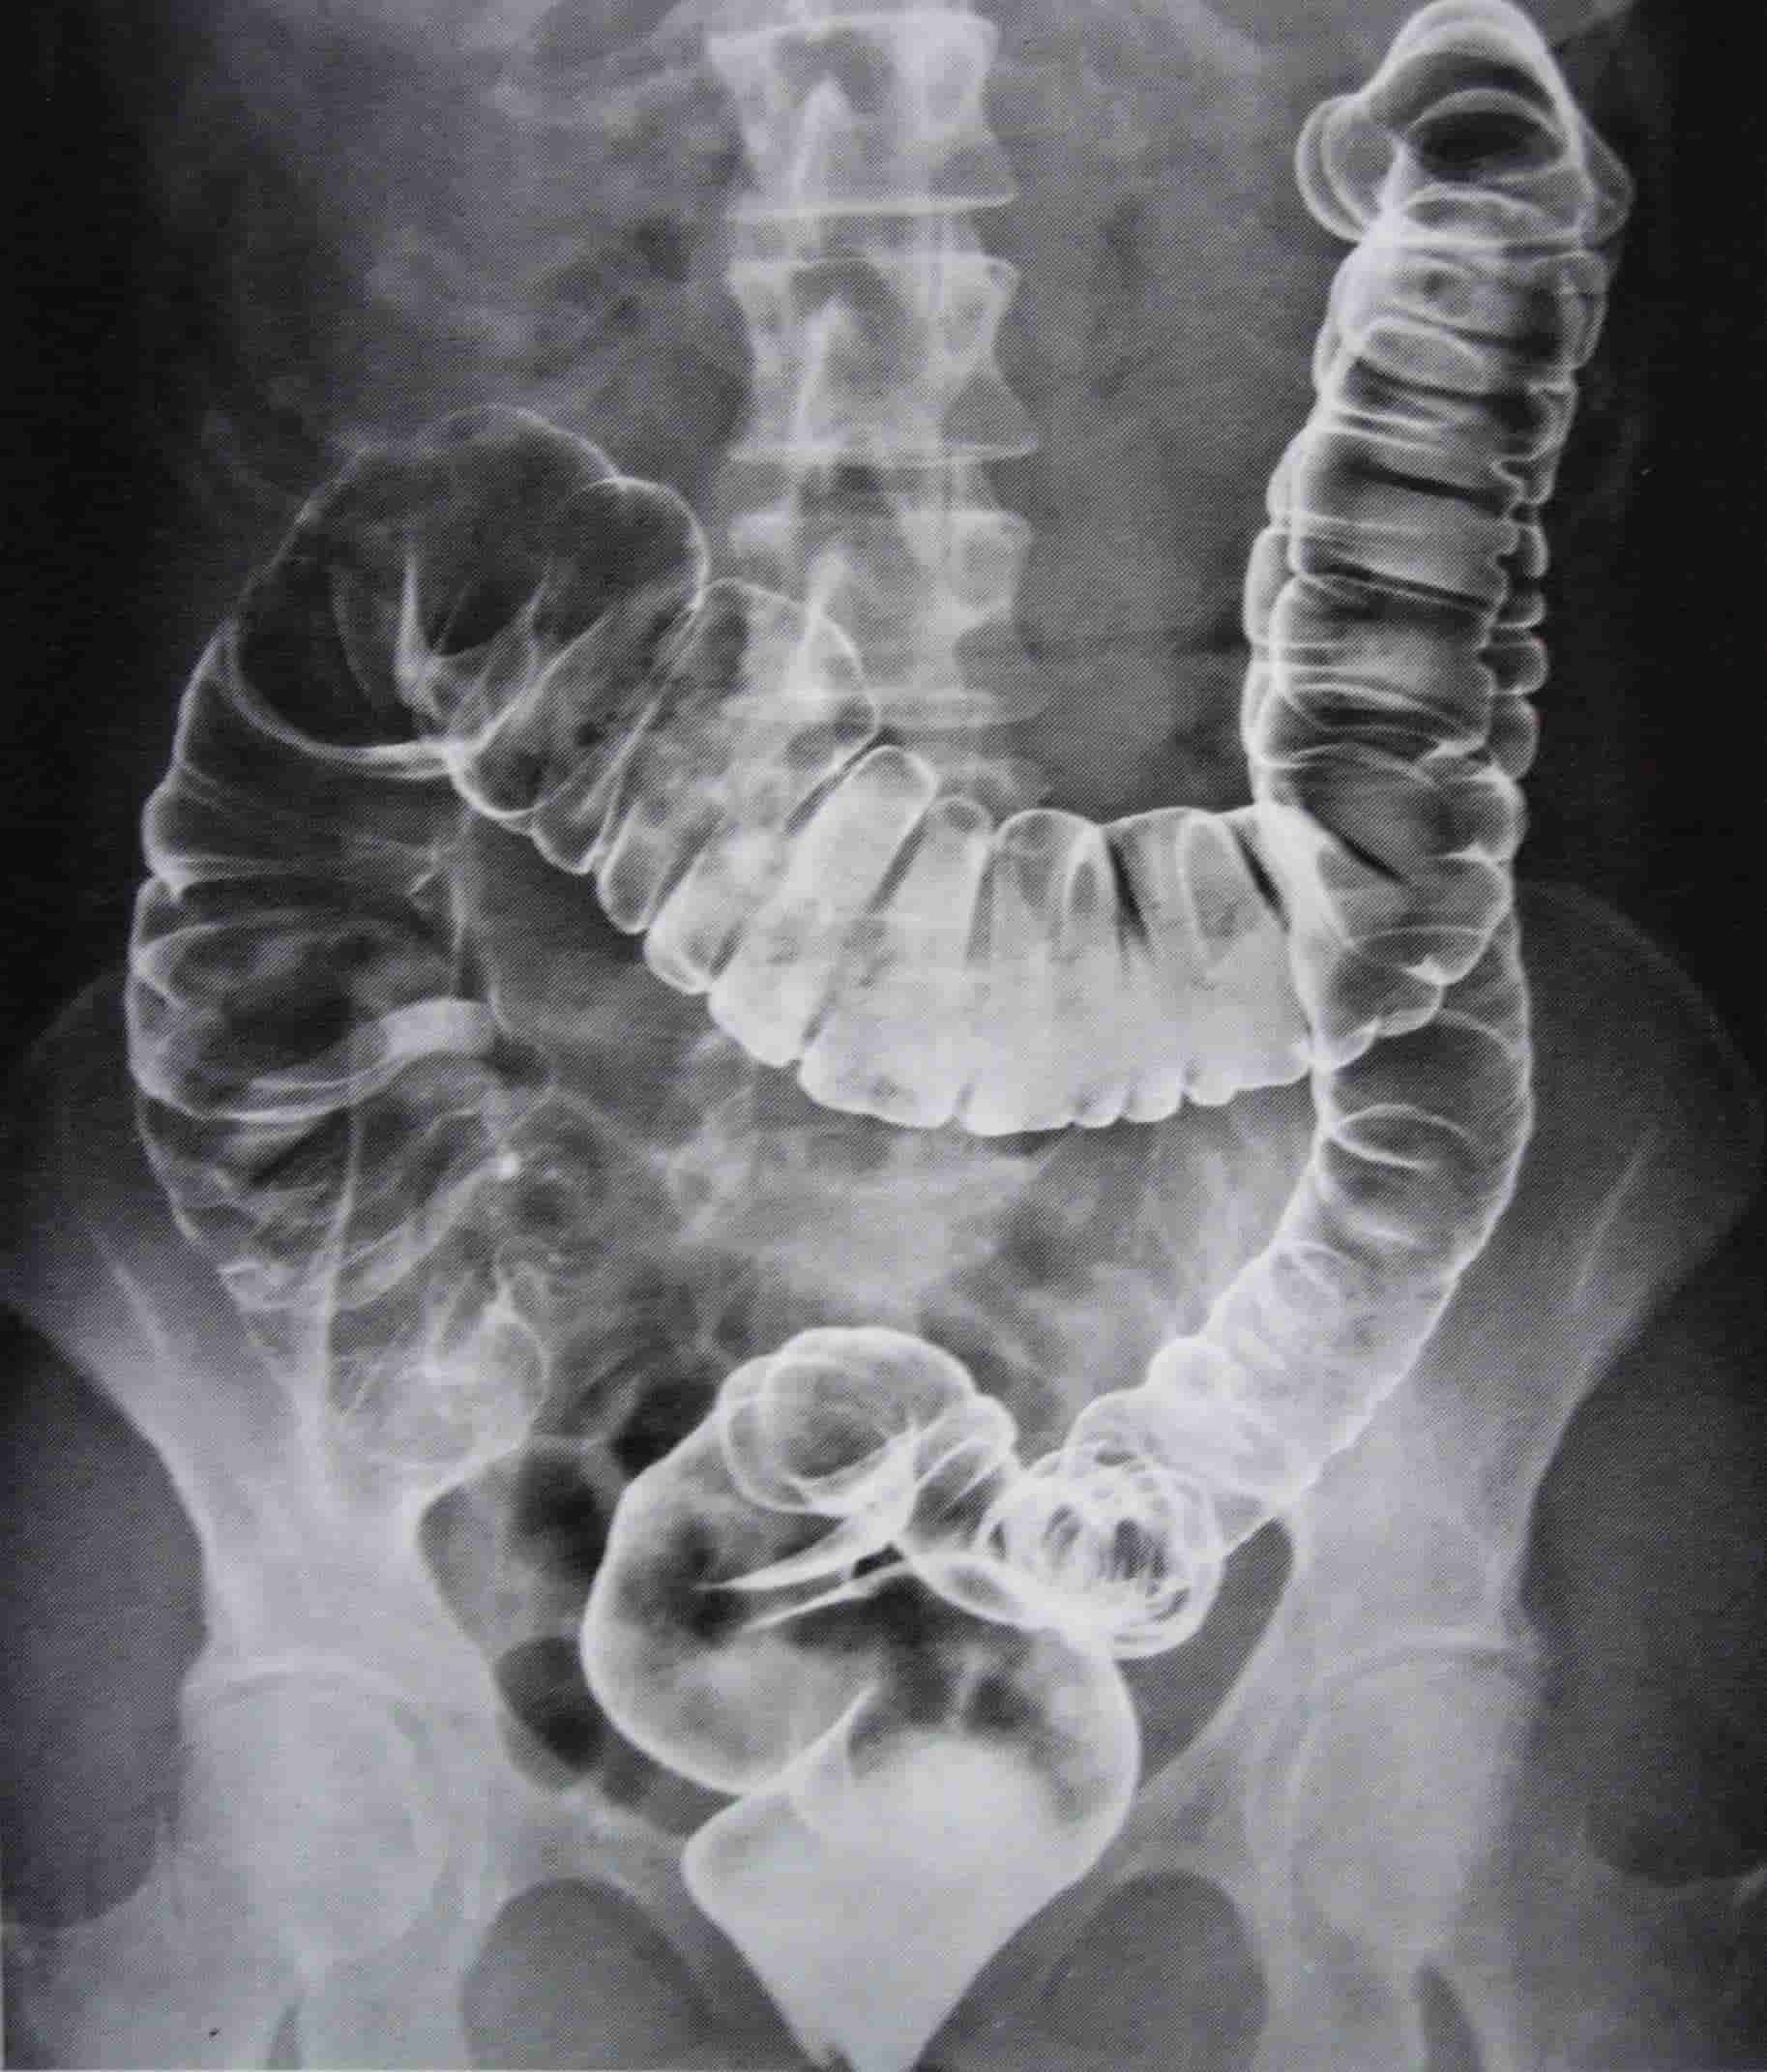

A doença de Crohn é uma condição inflamatória intestinal crônica que pode afetar qualquer parte do trato gastrointestinal, desde a boca até o ânus. Caracterizada por inflamação e ulceração do revestimento intestinal, ela causa dor abdominal, diarreia, perda de peso e outros sintomas que podem variar de pessoa para pessoa.

O diagnóstico da doença de Crohn é feito com base em uma combinação de fatores, incluindo: